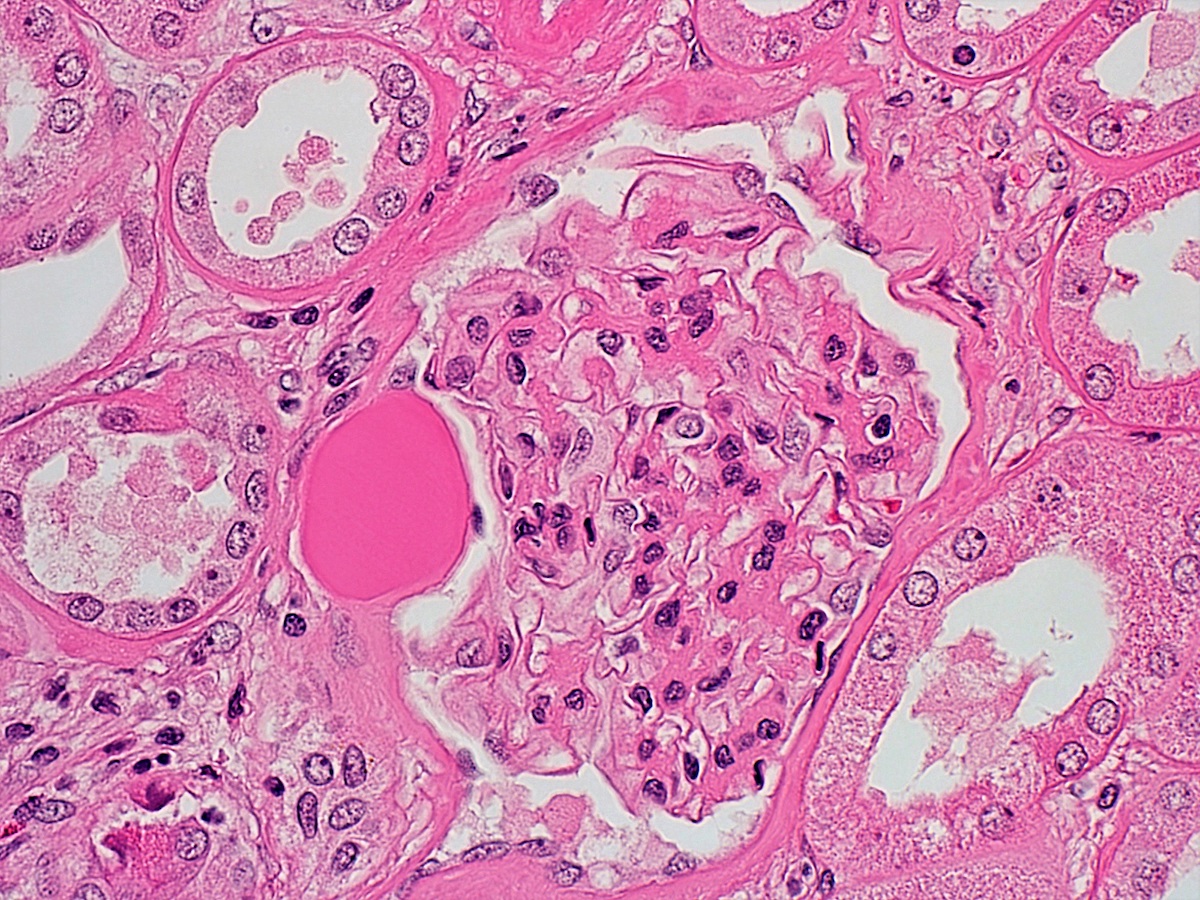

Microscopic (histologic) description

- Diffuse uniform thickening of glomerular basement membrane (GBM)

- Matrix expansion encroaching on the capillary lumina may be diffuse, nodular or both

- Nodular lesions are also called Kimmelsteil-Wilson lesions (Contrib Nephrol 2011;170:36)

- Microaneurysms of glomerular capillaries develop due to mesangiolysis

- These later give rise to large solitary nodules, which may reveal a laminated architecture on Jones silver stain

- Vascular hyalinosis is a common finding

- Hyalinosis of afferent and efferent arterioles usually seen but rare in other diseases

- Large subendothelial lipohyaline deposits may be present at the periphery of the glomerular tuft (hyaline caps)

- Similar deposits along the Bowman capsule capsular drops, which are specific

- In later stages, segmental glomerulosclerosis, especially at the tubular outlet tip lesion, is common

- Tubular atrophy, chronic interstitial inflammation and fibrosis, thickening of the tubular basement membranes

Microscopic (histologic) images

Contributed by Khaled A. Murshed, M.D., Noheir M. Taha, M.B.B.Ch., M.D. and Mohammed Akhtar, M.D.

A 57 year old woman was found to have proteinuria. A renal biopsy showed the findings in the image above (PAS). Which of the following conditions is the most important differential diagnosis?

Practice answer #1

E. Renal amyloidosis. The image shows diabetic kidney disease. In renal amyloidosis, mesangial nodules similar to those seen in diabetic kidney disease can occur. Answer A is incorrect because although lupus nephritis can have a wide morphological spectrum, mesangial nodules are very uncommon. Answer B is incorrect because in membranous glomerulonephritis, there will be mainly thickening of glomerular basement membranes. Answer C is incorrect because in minimal change disease, mesangial nodules do not occur. Answer D is incorrect because the main histologic change in postinfectious glomerulonephritis is endocapillary hypercellularity.